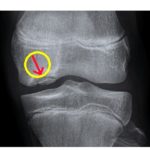

-Cartilage & Meniscus

Predictive Factors in Treating Chondral Defects of the Knee

Approach to Chondral Lesions of the Knee

Diagnosis and Treatment of Cartilage Lesions